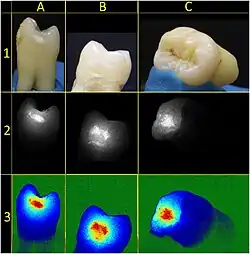

The presentation of caries is highly variable. However, the risk factors and stages of development are similar. Initially, it may appear as a small chalky area (smooth surface caries), which may eventually develop into a large cavitation. Sometimes caries may be directly visible. However, other methods of detection, such as X-rays, are used for less visible areas of teeth and to judge the extent of destruction. Lasers for detecting caries allow detection without ionizing radiation and are now used for the detection of interproximal decay (between the teeth).

Primary diagnosis involves inspection of all visible tooth surfaces using a good light source, dental mirror, and explorer. Dental radiographs (X-rays) may show dental caries before it is otherwise visible, in particular caries between the teeth. Large areas of dental caries are often apparent to the naked eye, but smaller lesions can be difficult to identify. Visual and tactile inspection, along with radiographs, are employed frequently among dentists, in particular to diagnose pit and fissure caries.[89] Early, uncavitated caries is often diagnosed by blowing air across the suspect surface, which removes moisture and changes the optical properties of the unmineralized enamel.

At times, pit and fissure caries may be difficult to detect. Bacteria can penetrate the enamel to reach dentin, but then the outer surface may remineralize, especially if fluoride is present.[91] These caries, sometimes referred to as "hidden caries", will still be visible on X-ray radiographs, but visual examination of the tooth would show the enamel intact or minimally perforated.

The early carious lesion is characterized by demineralization of the tooth surface, altering the tooth's optical properties. Technology using laser speckle image (LSI) techniques may provide a diagnostic aid to detect early carious lesions.[88]